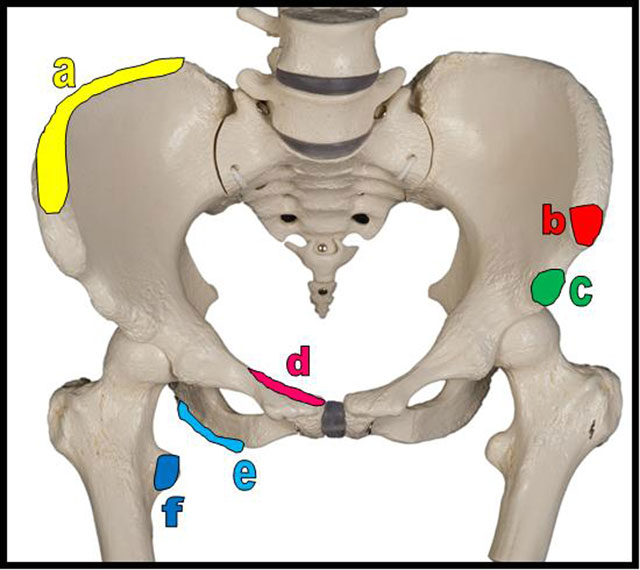

Figure 4

Schema of the most frequent sites of pelvic apophyseal avulsion fractures. a = iliac crest (insertions of the abdominal muscles, the tensor of fascia lata and of the gluteus medius); b = anterior superior iliac spine (insertion of sartorius); c = anterior inferior iliac spine (insertion of rectus femoris); d = superior corner of pubic symphysis (insertion of rectus abdominis); e = ischial tuberosity (insertion of hamstrings muscles = semitendinous, semimembranous and long head of the biceps femoris muscles); f = lesser trochanter (insertion of iliopsoas muscle).